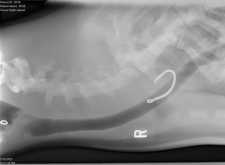

Each year, The Marine Mammal Center’s specially trained teams rescue marine mammals exhibiting signs of unfortunate run-ins with our trash. Typically, California sea lions are rescued with plastic netting, packing straps and other pieces of trash caught around their neck and face. Other animals have been rescued with plastic trash in their stomachs, such as plastic bags and balloons. These patients receive the highest quality of care at the Center’s state-of-the-art veterinary facilities.